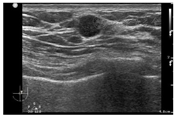

患者,男性,65岁,因右侧乳腺癌术后13年,左侧乳腺肿物10 d于2021年1月入我院。入院前当地医院行超声检查示:左侧乳腺体内低回声影,未行特殊治疗。患者高血压病史30年,血压最高200 mmHg/95 mmHg(1 mmHg=0.133 kPa),冠心病史1年,平时规律服用药物,日常控制尚可。糖尿病史3年,未行规律治疗。骨关节炎病史8年,未行特殊治疗。患者有乳腺癌家族史。查体:右乳缺如,有陈旧性手术瘢痕;左侧乳头未见脱屑,无内陷,无溢液;左侧乳房外上象限可扪及一肿物,距离乳头3 cm,大小约2 cm×2 cm,质硬,边界不清,活动度差,伴压痛;双侧腋下及锁骨上未扪及肿大淋巴结。超声检查见:右侧乳腺术后右侧胸壁未见明显占位性病变;左侧乳腺1点方向紧邻乳头旁可见低回声结节,大小0.9 cm×0.9 cm×1.0 cm,边界尚清,形态不规则,内回声不均匀,彩色多普勒血流成像(CDFI)检查示条状血流信号(图1)。超声提示:左侧乳腺实性结节BI-RADS 4A类。各项肿瘤标志物水平正常。患者行全身骨显像检查示:双膝关节代谢增高,考虑关节炎;无其他异常。